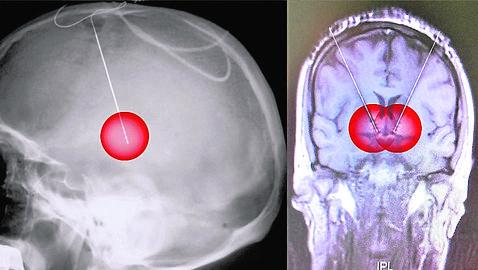

Operan con éxito, por primera vez, a una paciente implantándole dos electrodos en el cerebro que liberan estímulos eléctricos.